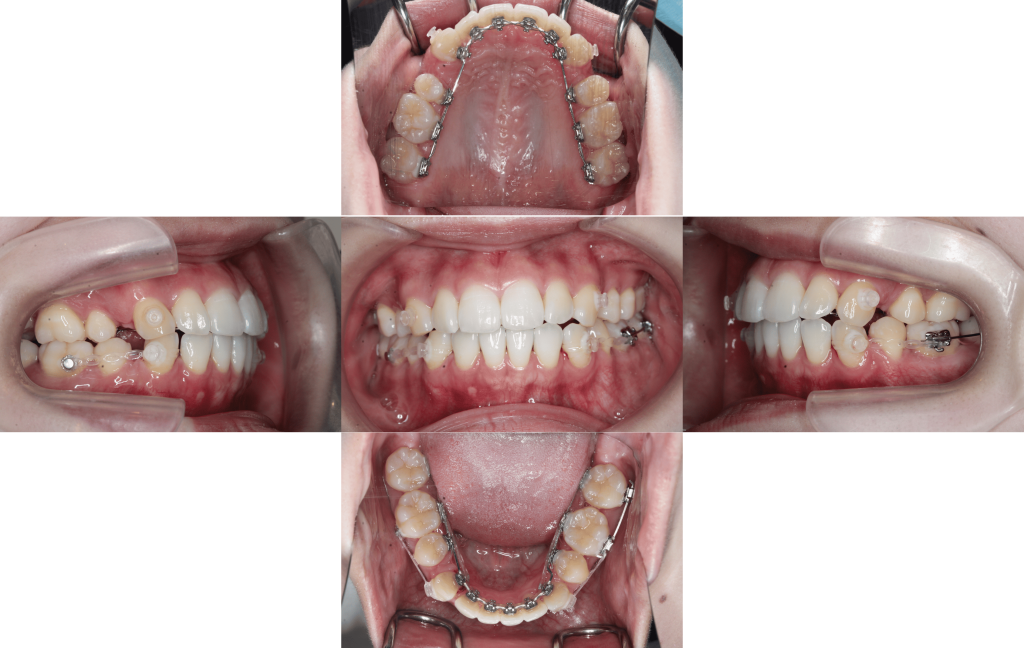

Before

装置装着